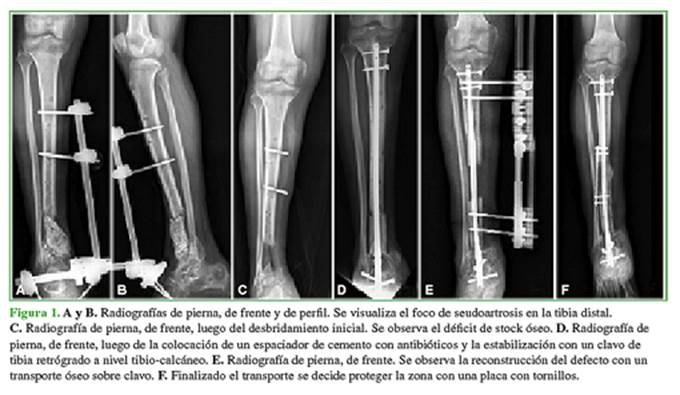

Hombre de 35 años con antecedentes de fractura expuesta de tibia distal con compromiso articular y pérdida ósea. Fue tratado en otro centro y evolucionó a una seudoartrosis infectada (Figura 1A-B).

Al ingresar en nuestra institución, fue sometido a un desbridamiento (Figura 1C), luego se le colocó un espaciador de cemento con antibióticos y se estabilizó con un clavo de tibia con colocación retrógrada a nivel tibio-talo-calcáneo (Figura 1D).

Ante una evolución favorable y luego del control del proceso séptico local, se procedió a la reconstrucción del defecto con un transporte óseo sobre clavo (Figura 1E).

Finalizado el transporte se decidió proteger la zona con una placa con tornillos (Figura 1F).